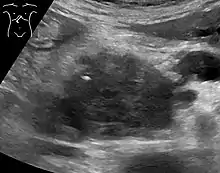

Medical imaging techniques, such as computed tomography (CT scan) and endoscopic ultrasound (EUS) are used both to confirm the diagnosis and to help decide whether the tumor can be surgically removed (its "resectability").[12] On contrast CT scan, pancreatic cancer typically shows a gradually increasing radiocontrast uptake, rather than a fast washout as seen in a normal pancreas or a delayed washout as seen in chronic pancreatitis.[56] Magnetic resonance imaging and positron emission tomography may also be used,[2] and magnetic resonance cholangiopancreatography may be useful in some cases.[32] Abdominal ultrasound is less sensitive and will miss small tumors, but can identify cancers that have spread to the liver and build-up of fluid in the peritoneal cavity (ascites).[12] It may be used for a quick and cheap first examination before other techniques.[57]